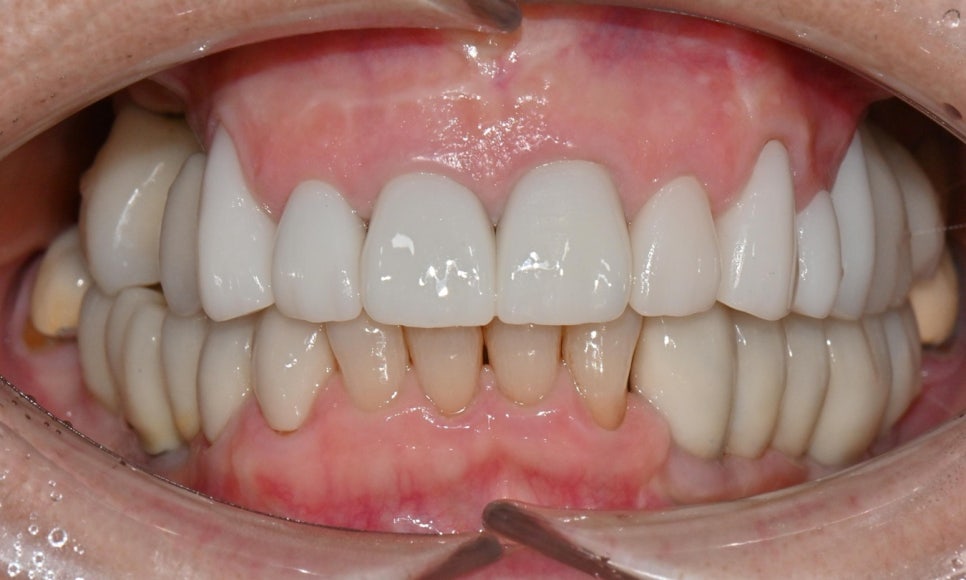

2026.2 치료 마무리 후 사진 - 연세정원치과

이와 같이 임시치아 단계에서 충분히 디자인을 조정하고 상담을 마무리하면, 기공소에 보다 정확한 디자인을 전달할 수 있어 최종 보철 만족도가 크게 높아집니다. 웃을 때나 말할 때 앞니 보철이 보이고, 아래 앞니도 추후 보철 예정이시라서 보철 색상은 다른 보철에 맞추기보다, 환자가 원하는 정도로 밝게 제작하였습니다.

치료 마무리 후 smile 사진 - 연세정원치과